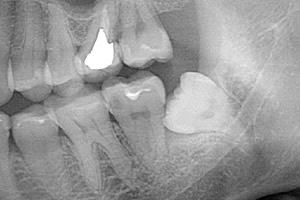

下の親知らずが歯ぐきから半分頭を出して生えている状態です。レントゲンで確認すると、親知らずがどのように生えているのかを確認できます。